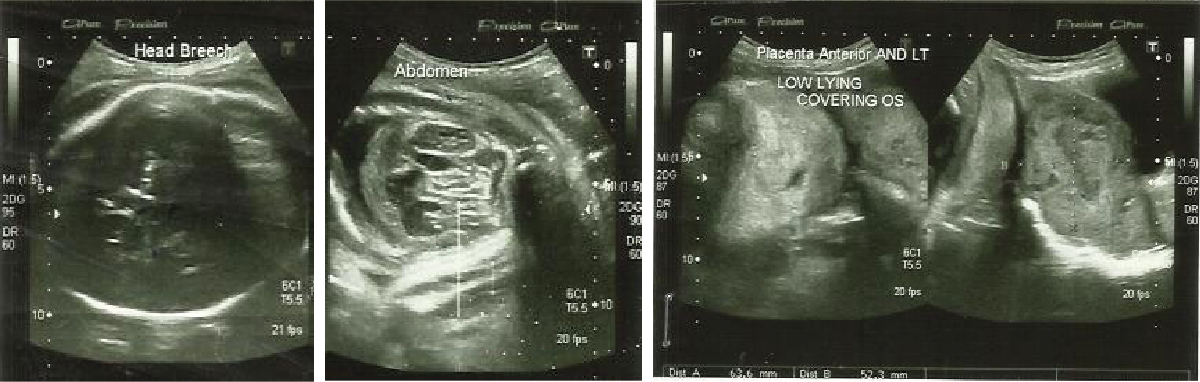

A 21-year-old woman with 37 weeks

2 days pregnancy presents with loss of fetal movement and pain in abdomen

since 3 days. On general examination: patient was of average built with

marked pallor, pulse 120/min, and blood pressure 100/60 mmHg. Respiratory and

cardiovascular system did not reveal any abnormality. Per abdominal

examination: heights of uterus 34 weeks, tenderness present, lower pole empty,

fetal heart sound were absent. Per vaginum examination: OS closed, cervix long

uneffaced. Investigation: hemoglobin 5 g/dL, blood group AB –ve, bleeding

time 2 minutes 15 seconds, and clotting time 3 minutes.

a) Abruptio placentae

b) Ruptured uterus

c) Fetal death

d) Both (b) and (c)